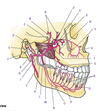

Deep Face (Part I) Flashcards

(242 cards)

A

Zygomatic process (of temporal bone)

B

Tubercle (of temporal bone)

C

Groove for deep temporal vessels (of temporal bone)

D

Postglenoid tubercle (of temporal bone)

E

Supramastoid crest (of temporal bone)

F

Suprameatal spine (of temporal bone)

G

Opening of external acoustic meatus (of temporal bone)

H

Tympanomastoid fissure (of temporal bone)

I

Mastoid process (of temporal bone)

J

Tympanic part (of temporal bone)

K

Vaginal process (of temporal bone)

L

Styloid process (of temporal bone)

M

Angle (of mandible)

N

Ramus (of mandible)

O

Condylar process (head and neck)(of mandible)

P

Mandibular notch and coronoid process (of mandible)

Q

Anterior (surface of maxilla)

R

Infratemporal (surface of maxilla)

S

Zygomatic bone

T

Zygomatic arch

U

Frontal bone

V

Greater wing of sphenoid

W

Squamous part of temporal bone

1

Articular tubercle